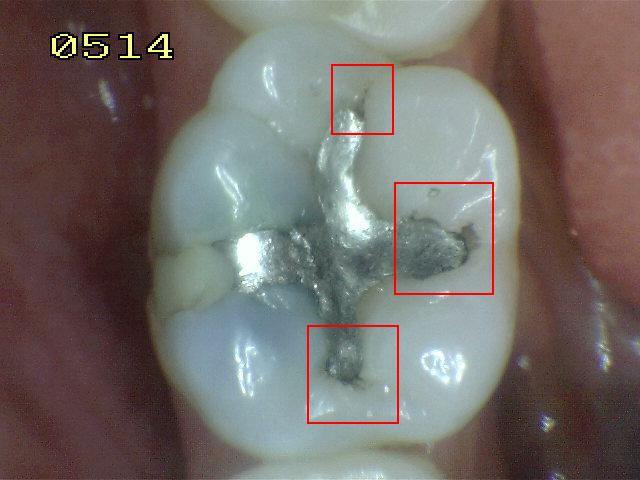

Código 4

(Caries Moderada): Sombra oscura

de dentina subyacente al esmalte intacto con o sin interrupción

localizada del esmalte

- La superficie de los dientes

puede tener características de código 2 y tiene una

sombra de dentina con cambio de color que es visible a

través de una superficie de esmalte aparentemente

intacto o con ruptura localizada en el esmalte pero sin

dentina visible. Este aspecto se ve más fácilmente

cuando el diente está húmedo y es una sombra oscura e

intrínseca que puede ser de color gris, azul, naranja o

café.

- Nota: observar el diente húmedo y luego seco. Esta

lesión debe distinguirse de sombras ocasionadas por

amalgama.